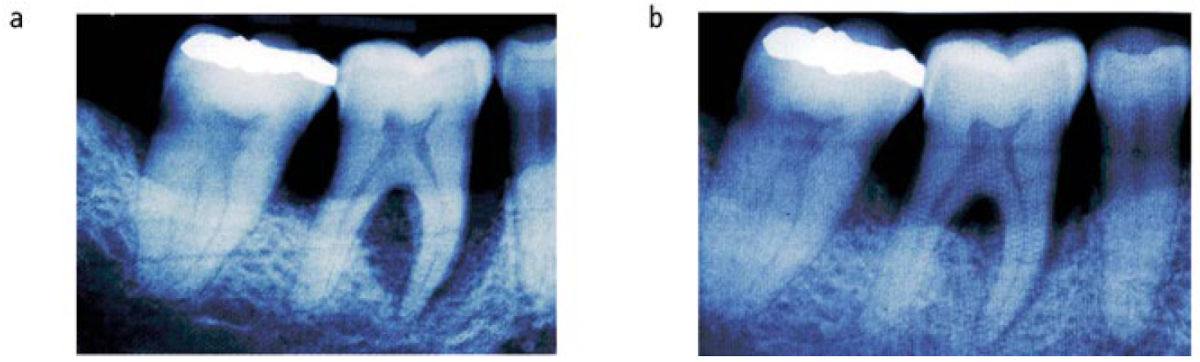

Ниже показан клинический случай, в котором было проведено только нехирургическое лечение пародонта. На первый взгляд зуб мог бы считаться безнадёжным, но благодаря эффективной терапии глубина пародонтальных карманов значительно уменьшилась, а на рентгенограммах видны признаки восстановления костной ткани.

Фото 3. Нехирургическое пародонтологическое лечение: (a) До лечения; (b) Через шесть месяцев после лечения